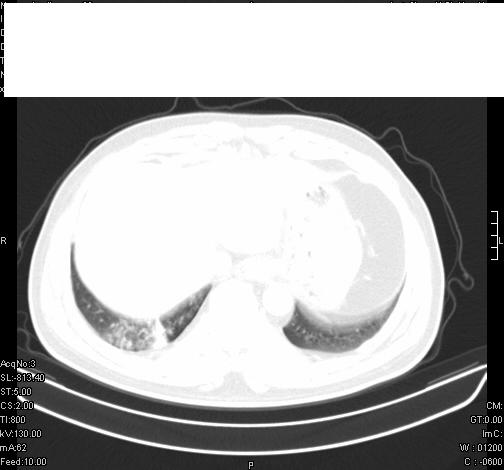

标题: CT6685:右肺阻塞性炎症,增强CT。

前几天,发了患者的平扫片,患者抗炎一周后增强扫描。右中叶病灶吸收明显,但下叶病灶未见明显吸收。右肺门可见结节影,看来凶多吉少

第18幅,好像不能简单用炎症解释,前几天我发平扫时,90%人支持肺癌,现在好像大家更倾向于炎症了,我觉得还是不能排除肺癌。

右肺下叶支气管壁不规则增厚,右肺下叶有斑片状影分布。考虑右肺中央型肺癌伴右肺下叶阻塞性改变。建议支纤镜检查。平扫比增强较好显示了病变情况。

右主支气管狭窄,管壁增厚。考虑右中心性肺ca伴阻塞性肺炎。

既然抗炎治疗有效,可继续治疗;右肺下叶支气管管腔狭窄,管壁增厚,右下肺见斑片状高密度影,右侧主支气管后见结节影(淋巴结?),肺癌不能排出。